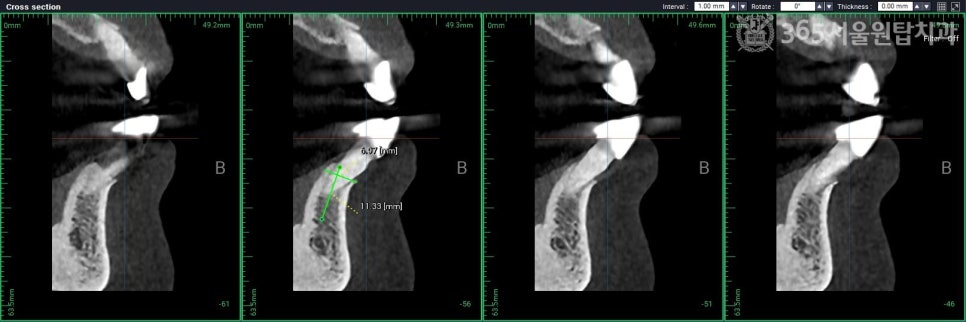

4)정밀한 디지털 설계

3D CT와

구강 스캐너 데이터를 기반으로

모의 수술을 거치기 때문에

식립 오차를 최소 수준으로 낮춥니다.

1)정밀 진단 (Pre-op)

파노라마, CT, 구강스캐너와 같은

3D 디지털 장비를 통해

치조골의 양, 골밀도, 신경관의 위치를

입체적으로 분석합니다.